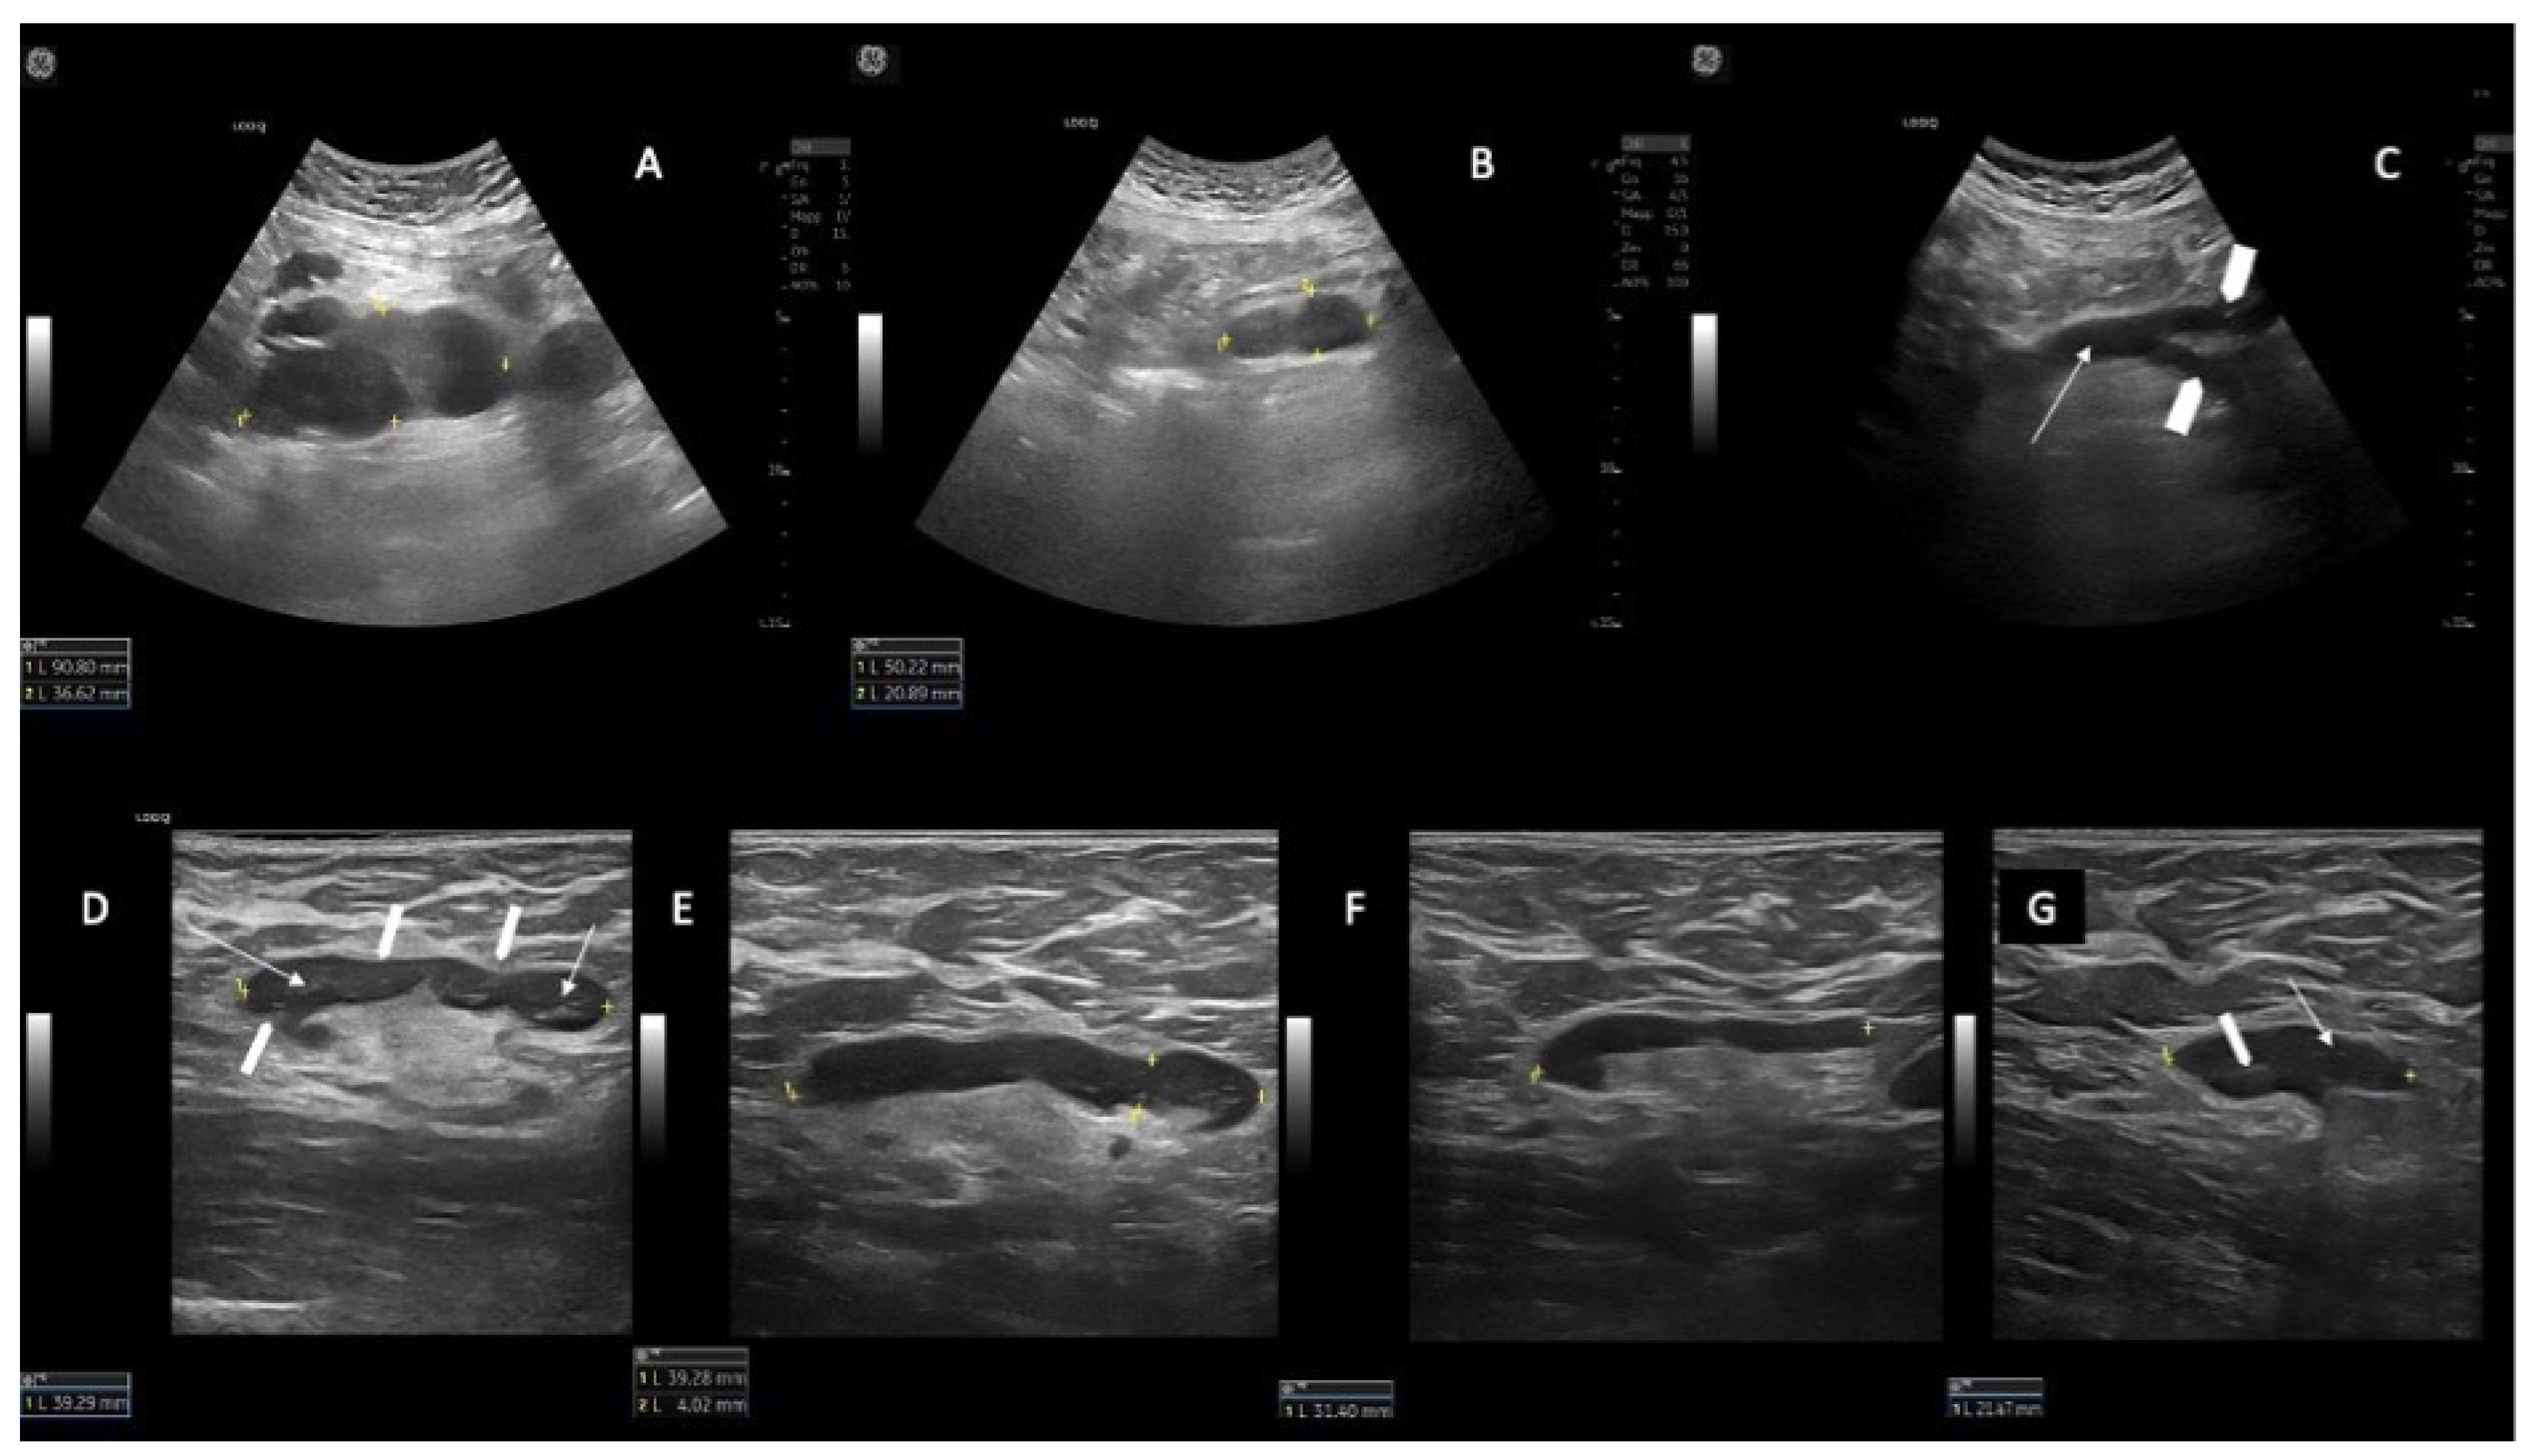

In patients whose response at time of the US assessment was PR (N = 6/22), we found that if the spleen and AbdLNs were pre-treatment involved, they obtained CR. Nevertheless, patients were considered in PR because of the persistence of superficial CLL diseased LNs (Figure 2).

Figure 2.

Example of AbdLN in CR but with persistence of CLL diseased SupLN (PR) in the same patient. (A) AbdLNs (longitudinal US scan with a convex probe) at baseline (T0) (90.1 mm). (B) the same AbdLN at T3 (50.2 mm). (C) disappearance of AbdLN (CR) at T6. The abdominal aorta is shown in a longitudinal scan (white arrow) and the right and left iliac arteries are visible (white arrowheads). (D) example of a right axillary CLL-SupLN at T0 (39.2 mm); the LN has an oval shape (long axis/short axis (L/S) > 2), the cortex is thickened, inhomogeneous, and reticulated (white arrows), which determines the lobular profile of the LN (white arrowheads). (E–G) the same right axillary CLL-SupLN at T6 (39.2 mm) (E), T12 (31.4 mm) (F) and T18 (21.5 mm) (G). In panel G there is still a partial involvement by CLL: the LN has oval shape (L/S > 2), the cortex is thickened and inhomogeneous and reticulated (white arrow), and the posterior part more thickened than the anterior part). The hilum is visible but is compressed and dislocated by the thickened cortex.